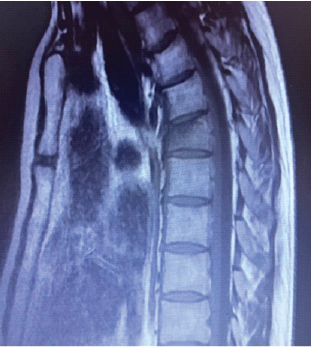

Aneurysmal Bone Cyst of Thoracic Spine in an Elderly Treated by Two Stage 360° Surgical Excision and Reconstruction with Expandable Cage – A Case Report

T S Nidhin , Ashok Thomas , V Vignesh Kumar , P P Nayar , Davis John

………………………………p.178-181